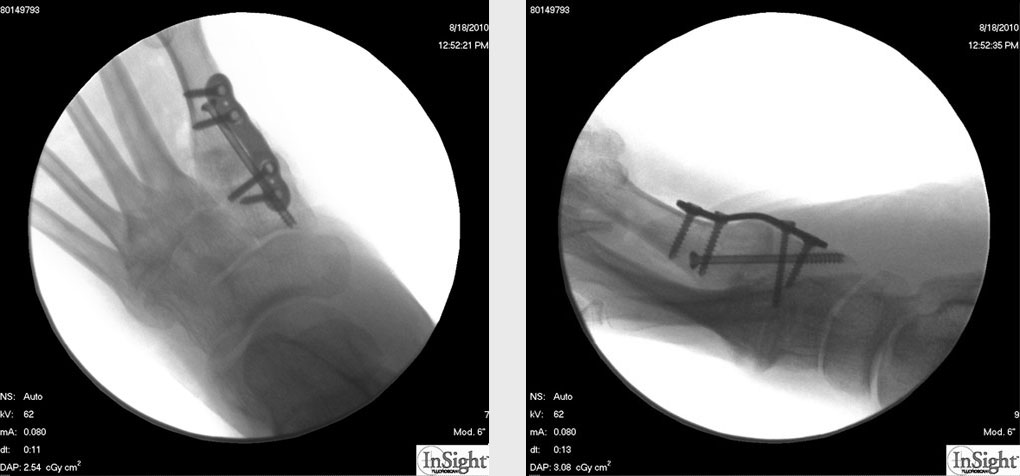

6 Wochen postoperativ Röntgenkontrolle in 4 Ebenen (dorsoplantar, lateral, 45° schräg von medial und lateral). Erscheint die Überbauung noch nicht ausreichend, erfolgt die Mobilisation im „Post-OP-Schuh“ für weitere 2 Wochen mit anschließender erneuter Röntgenkontrolle.

Pseudarthrose: Kommt es innerhalb von 6 Monaten zu keiner knöchernen Durchbauung, ist eine operative Revision indiziert. Ist anhand der normalen Röntgenaufnahmen in 4 Ebenen die Arthrodese nicht sicher zu beurteilen, kann mit Hilfe eines Computertomogramms die Überbauung sicher eingeschätzt werden (Abb. 12). Nach Ausräumung der Pseudarthrose und Spongiosaanlage vom Beckenkamm erfolgt die Reosteosynthese mit einer winkelstabilen Platte. Die Nachbehandlung nach Pseudarthrose umfasst eine 6-wöchige Phase der Entlastung im Castverband. Anschließend Belastungsaufbau nach Röntgenkontrolle. Insgesamt ist die Pseudarthrose eine seltene Komplikation der Arthrodese des TMT 1-Gelenks mit plantarer Osteosynthese.

Zum Lesen der Bildbeschreibung und zur Vollansicht bitte das Bild anklicken.

Abbildung 12